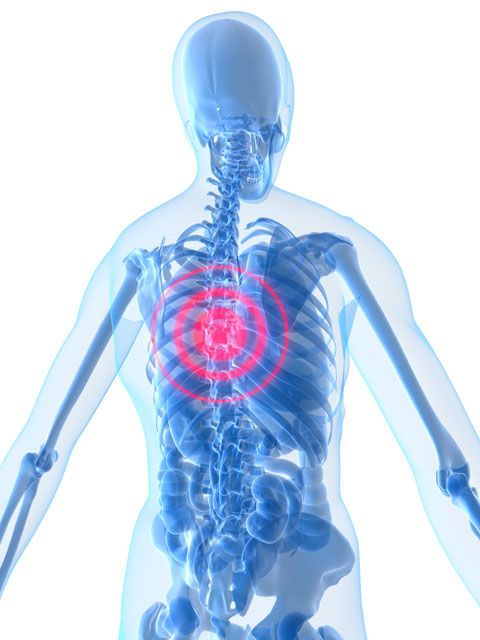

Are you regularly suffering from middle back pain below your neck and above the bottom of your rib cage? Referred to as the thoracic spine, this is one of the most common areas to experience chronic pain and a common reason why patients seek treatment with a chiropractor. Here is what you need to know.

Are you regularly suffering from middle back pain below your neck and above the bottom of your rib cage? Referred to as the thoracic spine, this is one of the most common areas to experience chronic pain and a common reason why patients seek treatment with a chiropractor. Here is what you need to know.

The thoracic spine or middle back is composed of twelve bones called the T1 to T12 vertebrae. In between these bones is what’s called disks. The job of this part of your body is to protect the spinal cord, and there are numerous muscles and nerves that can become injured or irritated in this region.